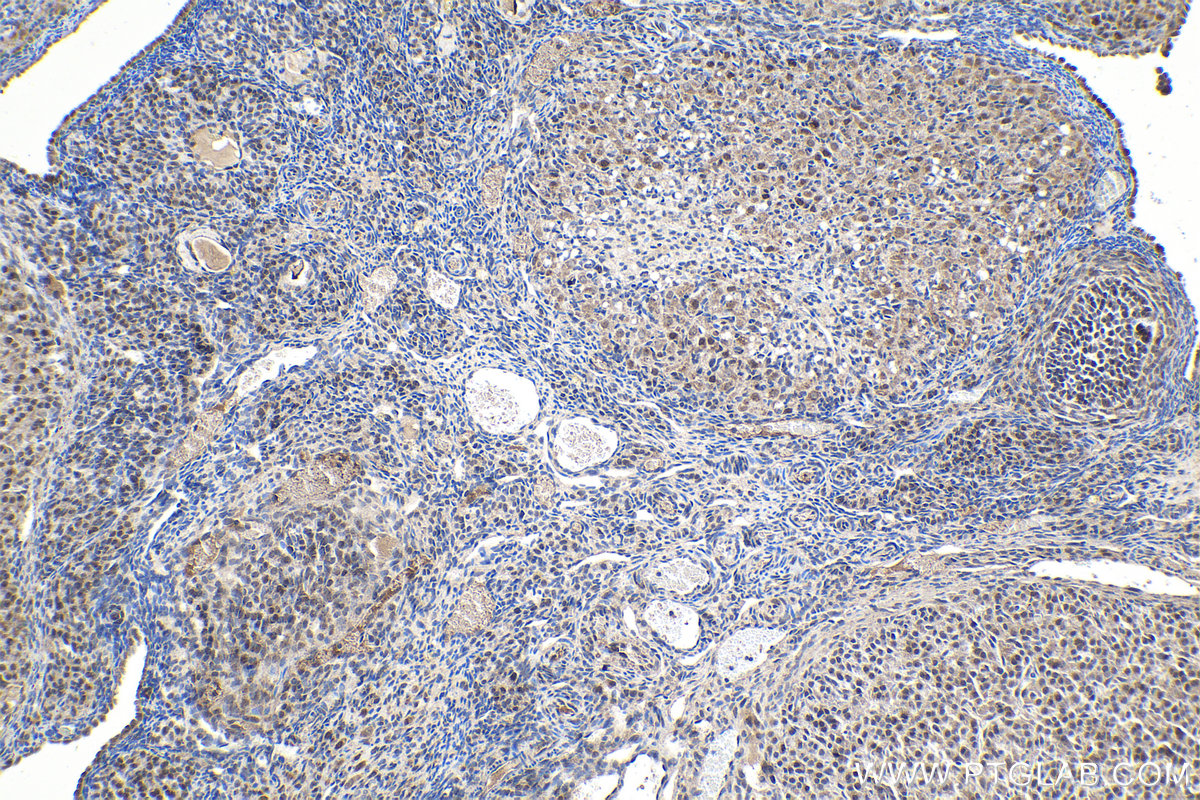

| Positive IHC detected in | rat kidney tissue, human thyroid cancer tissue, mouse kidney tissue, rat ovary tissue Note: suggested antigen retrieval with TE buffer pH 9.0; (*) Alternatively, antigen retrieval may be performed with citrate buffer pH 6.0 |

| Immunohistochemistry (IHC) | IHC : 1:500-1:2000 |